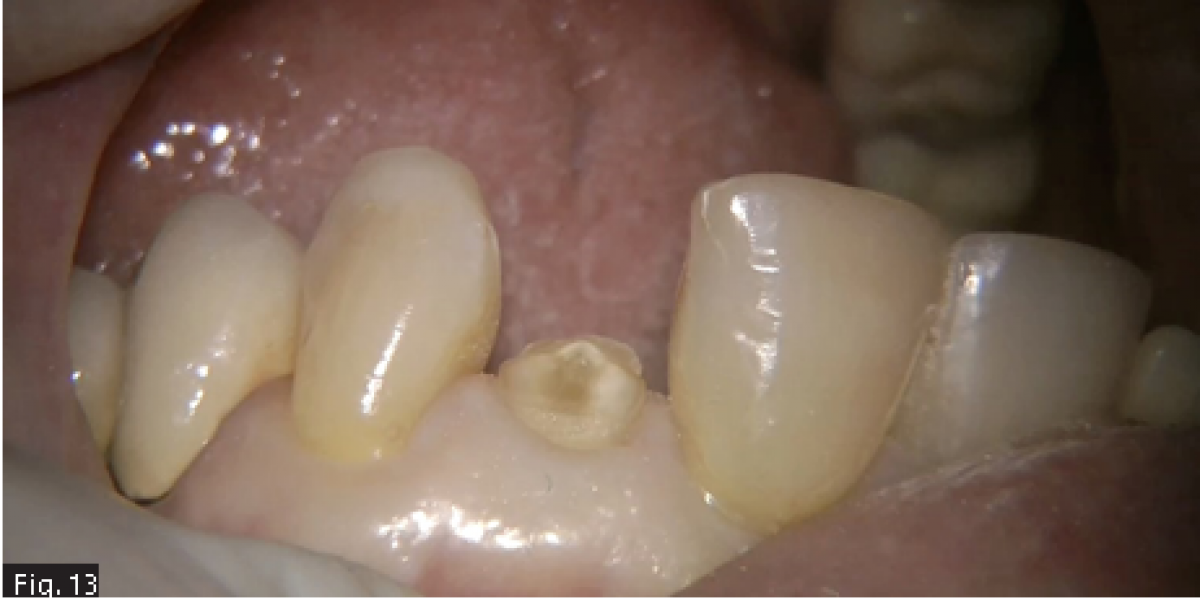

A 50 years old patient came to our office because of an emergency: while eating he broke the tooth 2.2 and he was not able to find the fragment (Fig. 13).

The fracture had exposed the pulp and the patient referred spontaneous and acute pain. The pre-operative x-ray showed that the tooth had a very thin canal lumen (Fig. 14) and a sufficient bone support, then it was decided to do an endodontic treatment followed by restoration and prosthetic crown.

As a first step of the therapy, rubber dam was positioned directly on the remaining tooth structure and the root canal treatment was started : the access cavity was designed and the root canal opening was found and enlarged with the help of ultrasonic tips. Then NiTi rotary instruments were used to complete the shaping of this narrow root canal space (Fig. 15). Multiple irrigation sequences were repeated using IrriFlex and ultrasonic activation of the sodium hypochlorite, both for making the endodontic instruments work in presence of an irrigating solution and to decrease the count of bacteria (20). The great advantage of using a polypropylene irrigation cannula was that, once the last shaping instrument reached the working length, also the cannula reached smoothly the working length (Fig. 16, 17), allowing to bring the irrigant as close as possible to the apical constriction of the root (1).